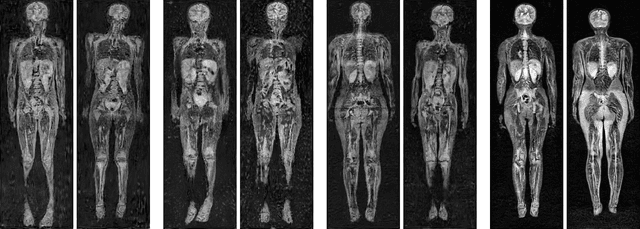

Abstract:Early detection of cancer is key to a good prognosis and requires frequent testing, especially in pediatrics. Whole-body magnetic resonance imaging (wbMRI) is an essential part of several well-established screening protocols, with screening starting in early childhood. To date, machine learning (ML) has been used on wbMRI images to stage adult cancer patients. It is not possible to use such tools in pediatrics due to the changing bone signal throughout growth, the difficulty of obtaining these images in young children due to movement and limited compliance, and the rarity of positive cases. We evaluate the quality of wbMRI images generated using generative adversarial networks (GANs) trained on wbMRI data from The Hospital for Sick Children in Toronto. We use the Frchet Inception Distance (FID) metric, Domain Frchet Distance (DFD), and blind tests with a radiology fellow for evaluation. We demonstrate that StyleGAN2 provides the best performance in generating wbMRI images with respect to all three metrics.